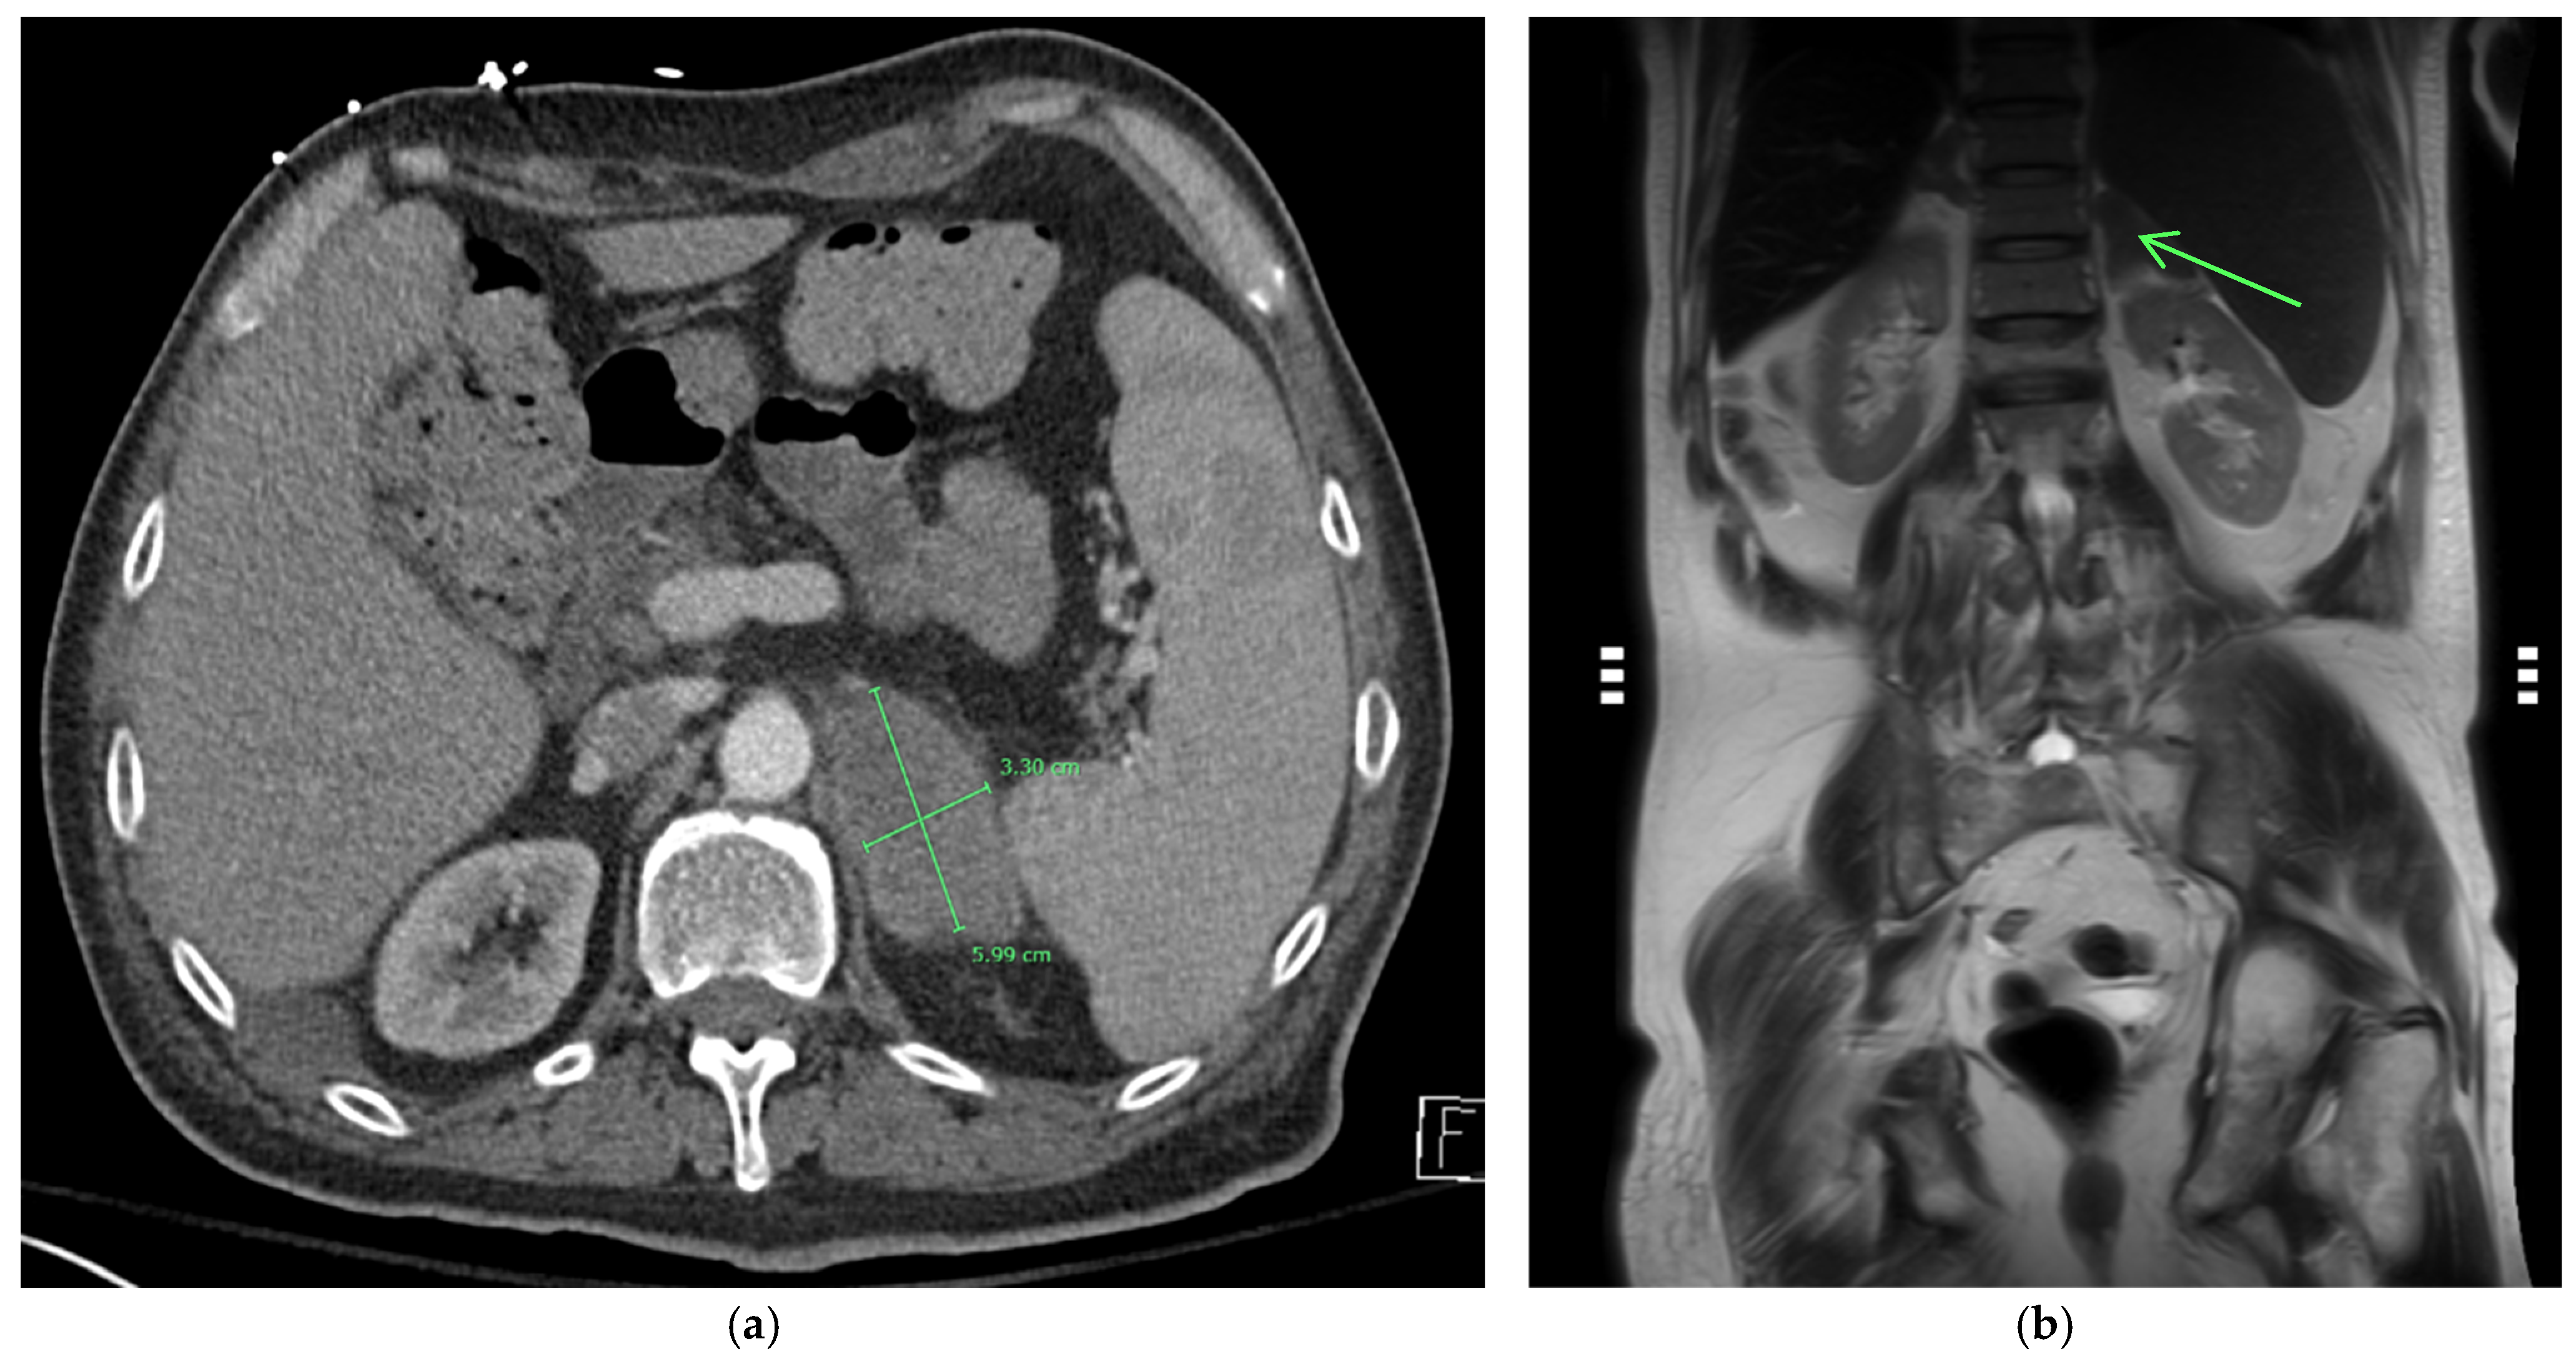

On admission, he was afebrile, saturating at 97% on room air, hypotensive with a blood pressure of 97/75, and tachycardic at 100 beats per minute, yet responsive to fluids. The physical exam was notable for a frail-appearing male with bilateral tongue nodular lesions that the patient described as painless and appeared several weeks prior to admission, see Figure 1. Due to concerns about malignancy, Oncology was consulted. Labs were significant for pancytopenia with a leukocyte count of 2.2 K/uL (NL 4–11 K/uL), hemoglobin of 12.4 g/dL (NL 13.5–17 g/dL), and platelet count of 114 K/uL (NL 130–450 K/uL). Absolute cell count showed a neutrophil count of 1.36 K/uL L (NL 1.5–7.8 K/uL) and lymphocytes of 0.49 K/uL L (NL 0.9–3.9 K/uL L). Computerized Tomography (CT) imaging of the chest, abdomen, and pelvis with contrast was significant for a left adrenal mass measuring 3.3 cm × 6 cm, see Figure 2a, which had increased from imaging 3 months prior showing a 3.2 cm × 3.5 cm mass. Imaging from 9 months ago did not show any mass. He also had a few scattered pulmonary nodules. Further work-up included Magnetic Resonance Imaging (MRI) of the abdomen and pelvis without contrast significant for diffuse thickening of the right adrenal gland up to 1 cm in the medial limb, the left adrenal mass of 6.6 cm × 3.8 cm, and splenomegaly, see Figure 2b. Due to adrenal masses, endocrinology saw the patient; he was found to have an elevated free normetanephrine level of 247 pg/mL (NL < 148 pg/mL) with a normal metanephrine range, not concerning for pheochromocytoma. The mildly elevated normetanephrine was thought to be physiologic since it was less than two times the upper limit of normal.

At the six-month follow-up, the patient reported significant improvement and resolution of all symptoms. Physical examination of the tongue showed resolution of the nodules and ulcerations (Figure 7). He had improvement in the repeat urine Histoplasma galactomannan antigen and falling Histoplasma yeast phase titers via CF. The Histoplasma antibody via immunodiffusion stayed negative. See Table 2 for a comparison of lab results. The patient had an abdominal MRI one year after his initial MRI, which showed improvement in the left adrenal mass from 3.3 × 6 cm to 2.8 × 3.7 cm (Figure 8). He is currently maintained on long-term itraconazole 200 mg TID.

Figure 2. (a) CT abdomen with contrast showing a large 3.3 × 6 cm enhancing left adrenal mass. (b) MRI imaging without contrast of the left adrenal mass demonstrates low T1 and T2 signals on the coronal MRI images (see arrow).

Figure 8. (a) MRI abdomen pelvis w/out contrast showing 2.8 × 3.7 cm enhancing left adrenal mass at 1-year follow-up. (b) MRI imaging without contrast of adrenal mass demonstrates low T1 and T2 signals on the coronal MRI images at 1-year follow-up (see arrow).